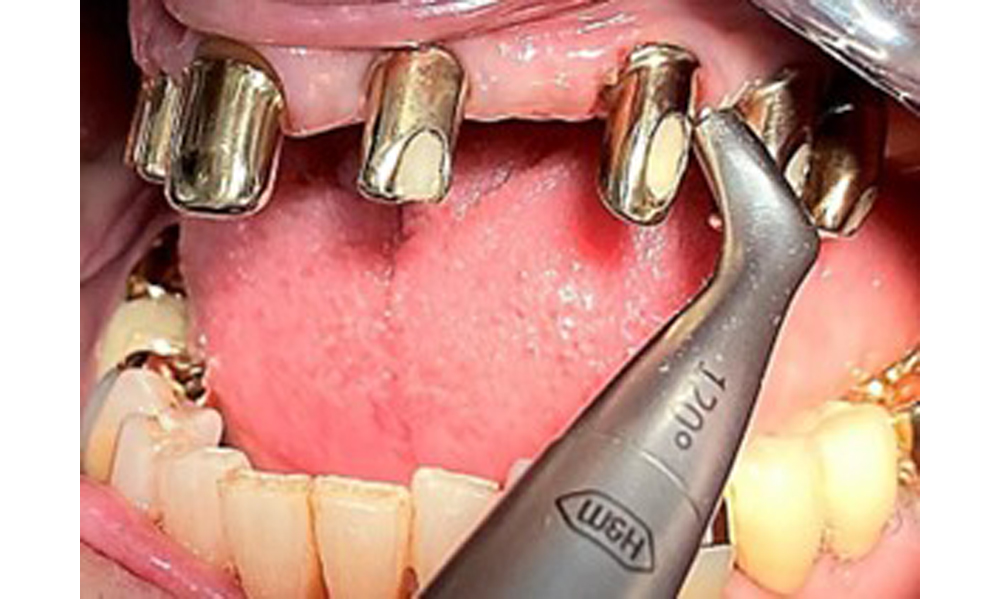

Processing the implant surface with manual titanium instruments.

Fig. 10: Processing the implant surface with manual titanium instruments.

Sonic/ultrasonic, or conventional manual instruments may be used to remove calculus and concretions present on the natural teeth (8). Titanium or plastic curettes (Fig. 10), or a plastic or PEEK attachment (Fig. 11) during ultrasonic treatment, should be used to remove mineralized plaque from implants to avoid damaging the implant surfaces.